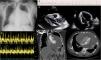

A 43-year-old man presented to the emergency department with a 2 week history of progressive breathlessness and fatigue. Physical examination revealed hypotension, tachycardia, jugular venous distension, pulsus paradoxus, and muffled heart sounds. His blood pressure was 90/60mm Hg, and the heart rate was 110 beats per minute. Chest x-ray showed a “water bottle configuration” suggestive of pericardial effusion (Fig. 1A). His electrocardiogram showed sinus tachycardia with small voltage QRS complexes and a degree of electrical alternans (Fig. 1B). Transthoracic echocardiography (TTE) revealed a large global pericardial effusion measuring>40mm in diameter with swinging of the heart freely in an anterior–posterior fashion (Fig. 1C, see video) and collapse of the right and left atria in end diastole, which was consistent with cardiac tamponade. Spectral Doppler demonstrated exaggerated respiratory variations of the mitral and tricuspid in-flow Doppler consistent with increased intrapericardial pressure and tamponade (Fig. 1D). A single axial, contrast-enhanced CT scan of the chest at the level of the heart showed a massive pericardial effusion (white arrows) surrounding the contrast-filled heart (LV=left ventricle) (Fig. 1E). The patient was immediately transferred to the coronary care unit where an emergency pericardiocentesis was performed which successfully drained 2.4 litres of serous pericardial fluid with immediate improvement of hemodynamics. Subsequent analysis showed a transudative pericardial fluid. All the connective tissue, cancer and infective markers were all negative and a diagnosis of idiopathic pericardial effusion was made. The patient was discharged well with resolution of the pericardial effusion on repeat TTE 4 days later. At 3 and 6 months follow-up, the patient was asymptomatic and well.